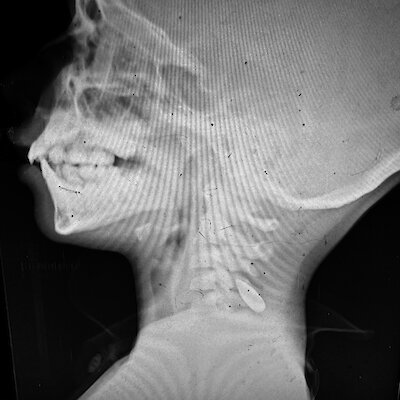

De Volkskrant przedstawił dwóm patologom sądowym dziesiątki zdjęć dzieci z ranami postrzałowymi oraz różne zdjęcia rentgenowskie. Potwierdzili oni, że rany zostały spowodowane przez pociski, a nie odłamki granatów. „Najprawdopodobniej chodzi o strzały oddane z dużej odległości, wymierzone w głowę i/lub szyję, przy użyciu amunicji wojskowej” – komentuje patolog sądowy Wim Van de Voorde, emerytowany profesor Uniwersytetu w Leuven. Według Van de Voorde zdjęcia nie są wystarczającej jakości, aby wyciągnąć wnioski prawne, „co jest zrozumiałe, biorąc pod uwagę bardzo trudne warunki lokalne”.

Patolog sądowy Frank van de Goot: „Na zdjęciach rentgenowskich widzę głowy dzieci z kulami w środku. Kule musiały stracić dużo energii po drodze, bo dzieci mają cieńsze czaszki niż dorośli, bo inaczej przeszłyby na wylot. Tak więc do tych dzieci strzelano z dużej odległości.

Wynik ten jest zgodny z zeznaniami naocznych świadków, którzy opisali lekarzom, że kule były zazwyczaj wystrzeliwane przez uzbrojone drony lub snajperów izraelskiej armii (IDF). Snajperzy mogą z dużej odległości, czasami nawet ponad tysiąca metrów, określić, kogo chcą trafić i gdzie. IDF nie chciała odpowiadać na pytania dotyczące strzelania do dzieci przez snajperów.